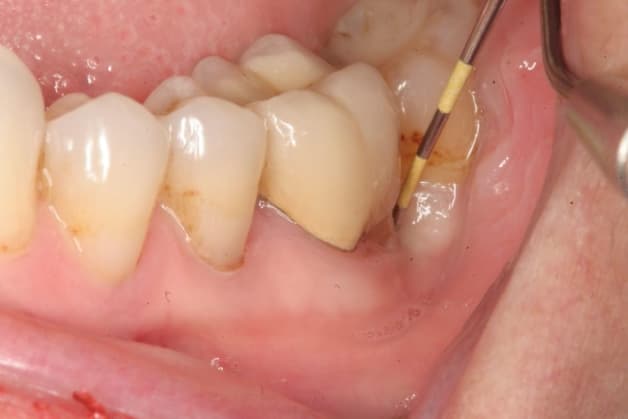

– Mảng bám là một lớp màu trắng hoặc vàng nhạt trên bề mặt răng, chứa hàng triệu vi khuẩn. Khi mảng bám không được loại bỏ đúng cách qua vệ sinh răng miệng hàng ngày, nó có thể kết hợp với các khoáng chất trong nướu và biến thành cao răng, làm kích thích nướu và gây viêm.

Phương pháp điều trị tại chỗ: Chuyên gia nha khoa sẽ sử dụng nước muối sinh lý kết hợp với betadine để thực hiện quá trình rửa sạch khu vực răng có mảng thức ăn đọng. Sau đó, việc chích rạch và tiến hành lưu mủ cùng dịch viêm sẽ được thực hiện.

Nha sĩ sẽ thăm khám và quyết định phương án đều trị cho răng của bạn